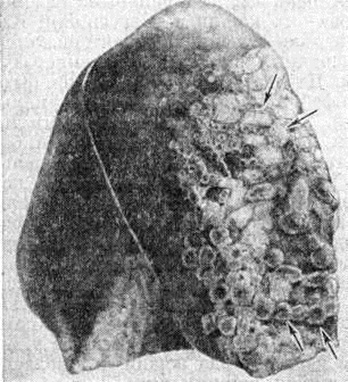

Воспалительные изменения лёгких обнаруживаются на фоне выраженных острых расстройств кровообращения в виде полнокровия, кровоизлияний, отёка; часто встречается инфильтрация межуточной ткани лёгкого лимфоцитами, нейтрофильными и эозинофильными лейкоцитами. Макроскопически лёгкие вздуты, образуются мелкие и крупные пузыри везикулярной эмфиземы, особенно в краевых отделах (рисунок 2). Возможна острая интерстициальная эмфизема и пневмоторакс. Передние отделы лёгких бледные, серо-розового цвета, задние — серо-красные с точечными кровоизлияниями. На разрезе ткань лёгких полнокровна, с многочисленными западающими темно-красными участками ателектазов. При наличии пневмонии определяются мелкие серо-красные фокусы уплотнения.